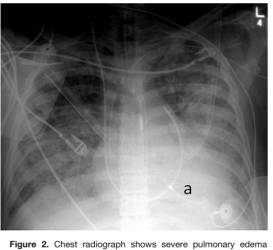

胸 片

肺水肿表现

袢利尿剂:静脉速尿,减轻肺水肿/肺淤血

缺点:LV 后负荷↑→ LVEDP、室壁张力↑→ LAP↑→ 肺水(可联用IABP、LVAD)